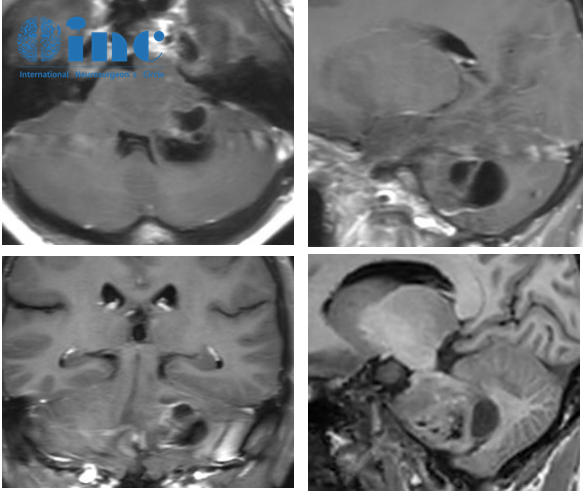

吴女士术前MRI

2019年初,脑核磁检查发现脑干胶质瘤,有轻微左眼跳,头部嗡嗡响的症状。症状发生频率低,脑鸣症状持续时间为1-2秒。3个月后加强核磁做完,于国内知名神外医生处就诊,最终诊断:延髓、脑桥异常信号:考虑为胶质瘤可能。随即被告知“先回家观察,定期复查核磁”。无奈之下,听取病友的意见,随后前往某中医院做中医调理。这些调理在标准治疗的面前或许只能算作偏方,“为什么用偏方?不就是没路可走,拼命找活路吗!”为了鼓励母亲,儿子和吴女士每天通过微信聊天,每周从学校回到家里,陪她散步、吃饭、聊天,这一切都让吴女士感觉很知足。

2020年初,时隔一年,症状加重,出现左侧部分面部麻症状,一段时间后麻感加重,累及整个左侧面部区域以及颈部、咽部、舌头等。最严重的时候由麻感转木感。吴女士难受的整夜整夜无法入睡,痛苦万分。一个月后,再次前往国内知名神外医生处就诊,回复依旧是“不建议动手术,回家观察”。随后只能再次到中医院进行中医调理,调理期间病情继续加重,又出现视野缺损、视物模糊、不敢快速转动头部、头晕等症状。

2021年8月,吴女士出现视物双影,睡眠不佳,脑鸣加重,眼前发黑,右眼中央有红点,视物模糊,头晕、恶心、呕吐。这一次就诊,医生表示,无法再保守治疗,必须手术了,但是手术只能切除小部分肿瘤,且面临术后瘫痪、意识障碍、呼吸抑制等巨大风险。术后还需辅助放化疗。手术,吴女士可能承担更大风险与病痛,不手术,吴女士又如何度过这倒计时的生命?这是摆在所有家属面前的一道选择题,也是一道令人难以作答的必答题……最终,一家人决定手术,且必须找世界顶尖的医生手术。